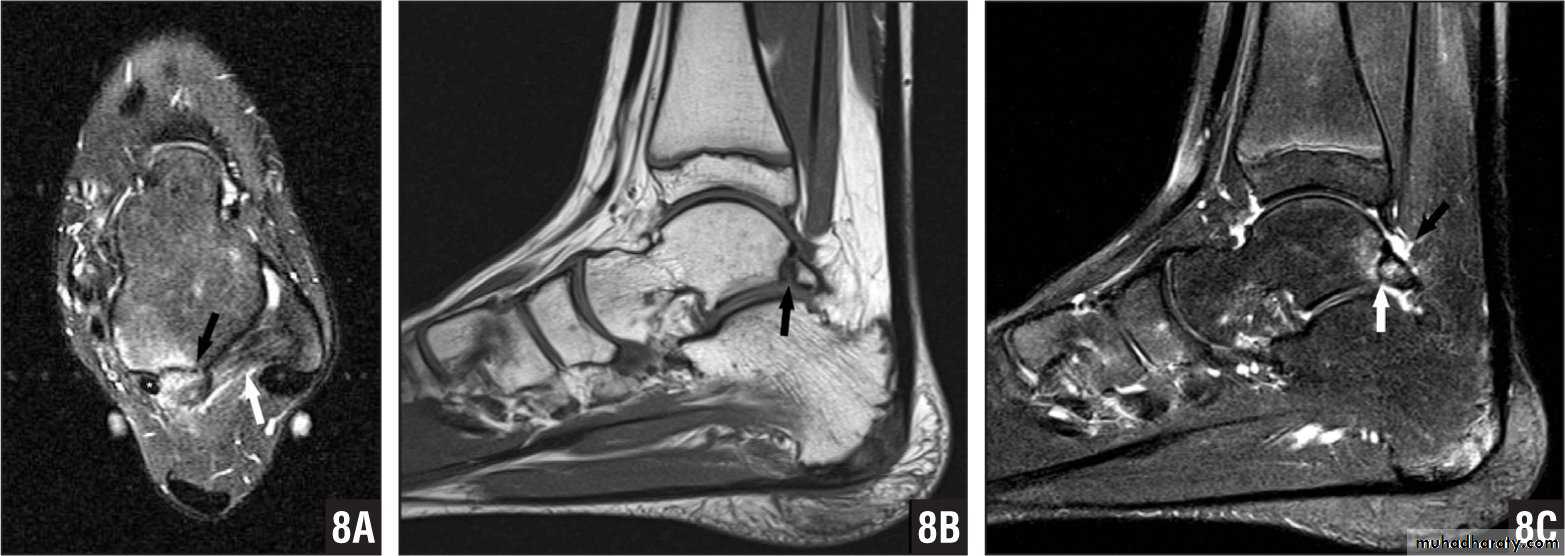

• Gradient- echo sequences are extremely sensitive to the presence of substances that cause local alterations in magnetic properties. Examples of such substances include iron-containing haemosiderin and ferritin found in chronic blood. It has known as susceptibility weighted imaging.

Functional MRI sequences

• Diffusion-weighted imaging (DWI) is sensitive to the random Brownian motion (diffusion) of water molecules within tissue. The greater the amount of diffusion, the greater the signal loss on DWI. Areas of reduced water molecule diffusion show on DWI as relatively high signal. Diffusion-weighted imaging is the most sensitive imaging test available for the diagnosis of acute cerebral infarction, epidermoid cyst and abscess.• Perfusion-weighted imaging (PWI) may be used in patients with cerebral infarct to map out areas of brain at risk of ischemia that may be salvageable with thrombolysis.

• Magnetic resonance spectroscopy (MRS) uses different frequencies to identify certain molecules in a selected volume of tissue, known as a voxel. Following data analysis, a spectrographic graph of certain metabolites is drawn. Metabolites of interest include lipid, lactate, NAA (N-acetylaspartate), choline, creatinine, citrate and myoinositol. Uses of MRS include characterization of metabolic brain disorders in children, imaging of dementias, differentiation of recurrent cerebral tumor from radiation necrosis, and diagnosis of prostatic carcinoma.

• Magnetic resonance angiography and magnetic resonance venography used for visualization of blood vessels with or without using contrast material.

• Imaging modality of choice for most brain and spine disorders• Musculoskeletal disorders, including internal derangements of joints and staging of musculoskeletal tumors